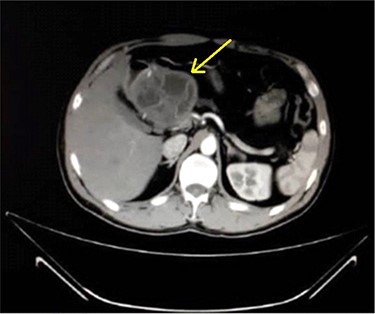

A 33-year-old male was referred to our Department of General Surgery, with a 3-month severe epigastric pain radiating to the back, associated with several episodes of green vomiting. Pain is episodic, relieved by painkillers, has no relation to food or movement. No history of changes in bowel habits or urine color. The patient reported a history of early satiety and an observed unmeasured weight loss. The past medical and surgical histories were irrelevant. Abdominal examination showed tenderness in the epigastric region, with no other signs. Laboratory tests including complete blood cell count, renal and liver function tests were within normal levels. Immunologic methods (ELISA) and indirect hemagglutination (IHA) assays were negative. Serum Amylase and CA 19-9 were within normal levels. Computed tomography (CT) scan revealed a multilocular cystic lesion in the head of the pancreas measuring 9.5 × 8.2 × 11 cm, causing external compression on the distal part of the CBD. The main pancreatic duct near the cystic mass is dilated measuring 0.5 cm. The gallbladder is distended (Figs 1 and 2).

Axial contrast-enhanced CT scan of the abdomen showing dilatation of the MPD (5 mm).